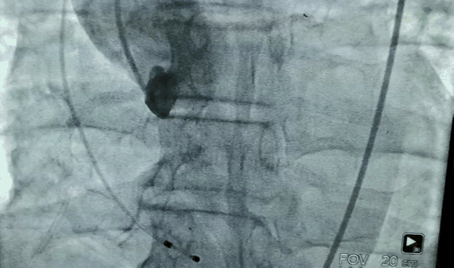

70岁女性,梅毒合并二叶瓣,主动脉瓣狭窄,肺部有肿瘤。

遵循传染病防治法,为病人排忧解难

由于有梅毒阳性,根据传染病防治法的要求,这例病人被放在了最后。